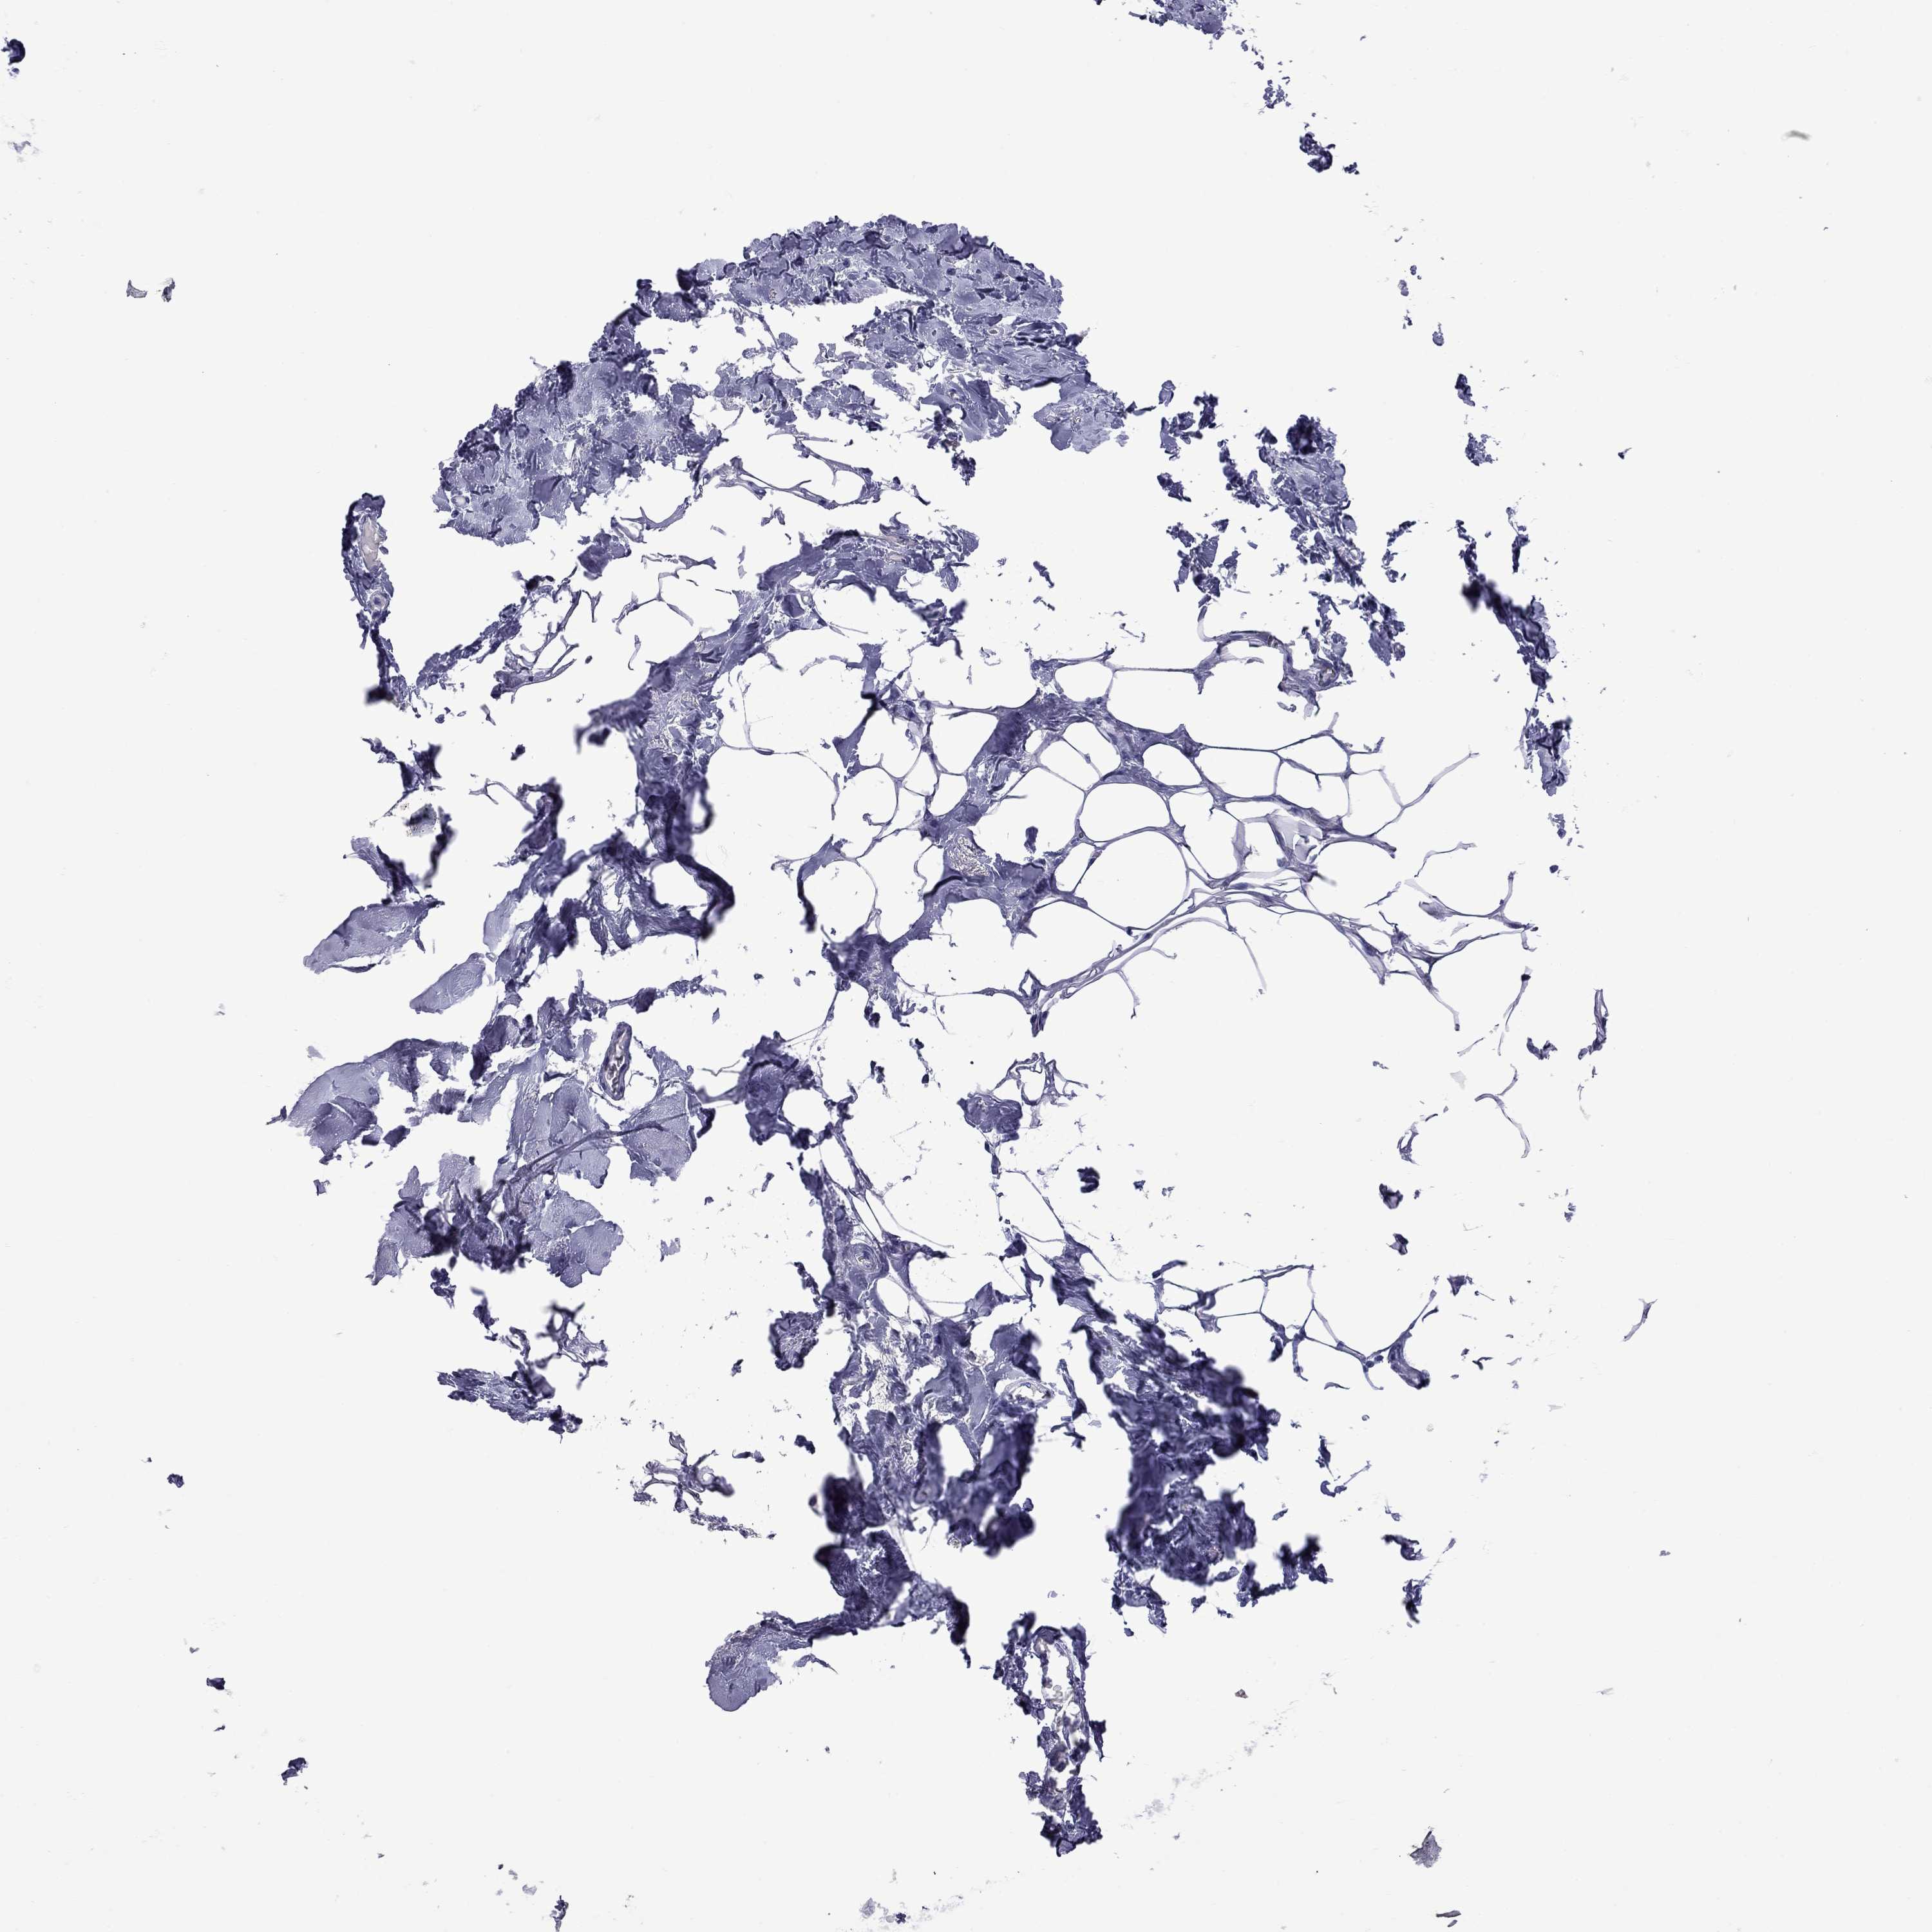

BRCA TCGA BRCA VALIDATION PROTEIN EXPRESSION